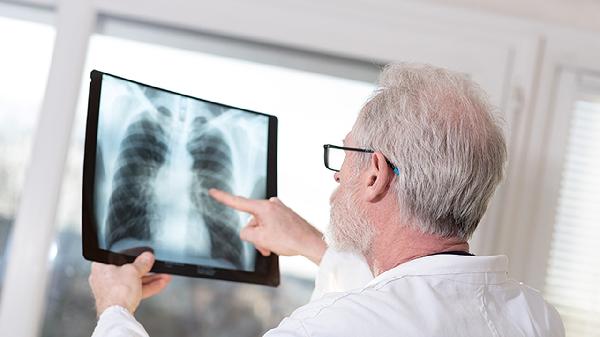

极少数免疫功能健全的个体接触少量结核菌后,可能通过自身免疫清除病原体,但这种情况无法预测且缺乏临床证据支持。多数无症状感染者需通过结核菌素试验、γ-干扰素释放试验或影像学检查发现病灶,确诊后应完成6-9个月的抗结核药物治疗。